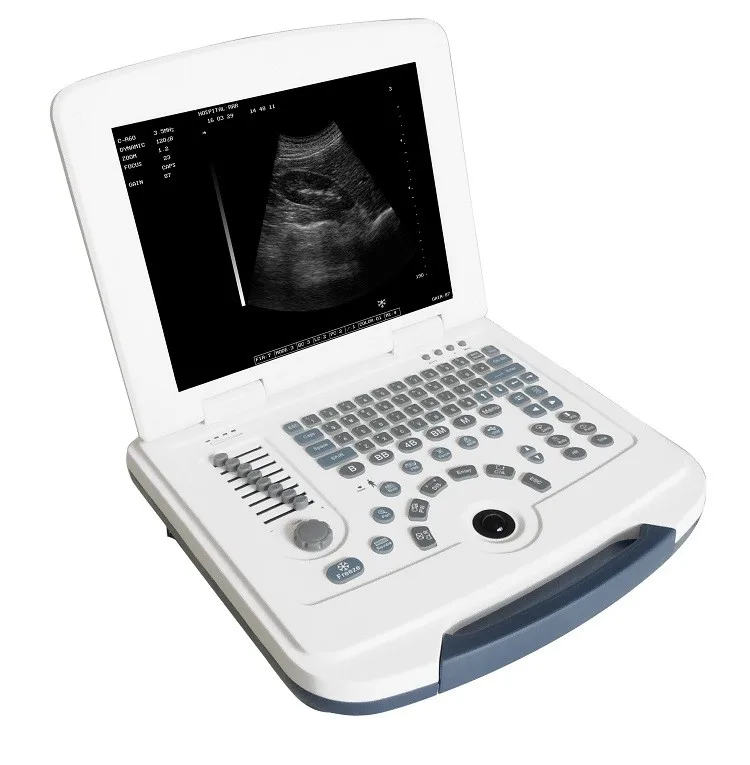

Portable ultrasound scanner 4d color doppler ultrasound wireless ultrasound